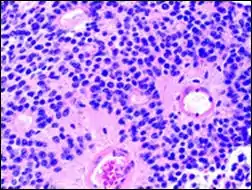

Micrograph of Homer Wright pseudorosettes

A Homer Wright pseudorosette is a type of pseudorosette in which differentiated tumor cells surround the neuropil.[15] Examples of tumors containing these are neuroblastoma, medulloblastoma, pinealoblastoma, and primitive neuroectodermal tumors of bone. Homer Wright rosettes are considered "pseudo" in the sense that they are not true rosettes. True rosettes are Flexner–Wintersteiner rosette, which contain an empty lumen. Homer Wright rosettes contain abundant fibrillary material. They are named for James Homer Wright.